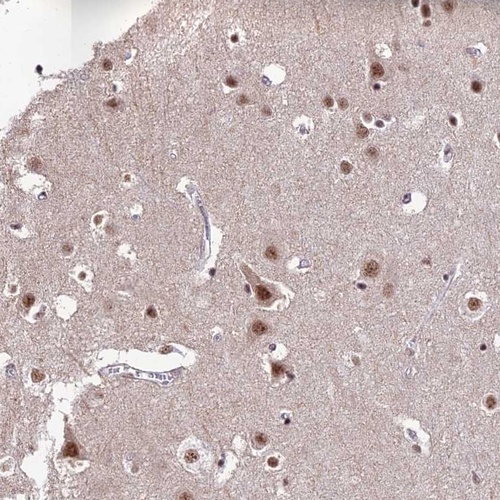

Immunohistochemical staining of human cerebral cortex shows moderate nuclear positivity in neuronal cells.